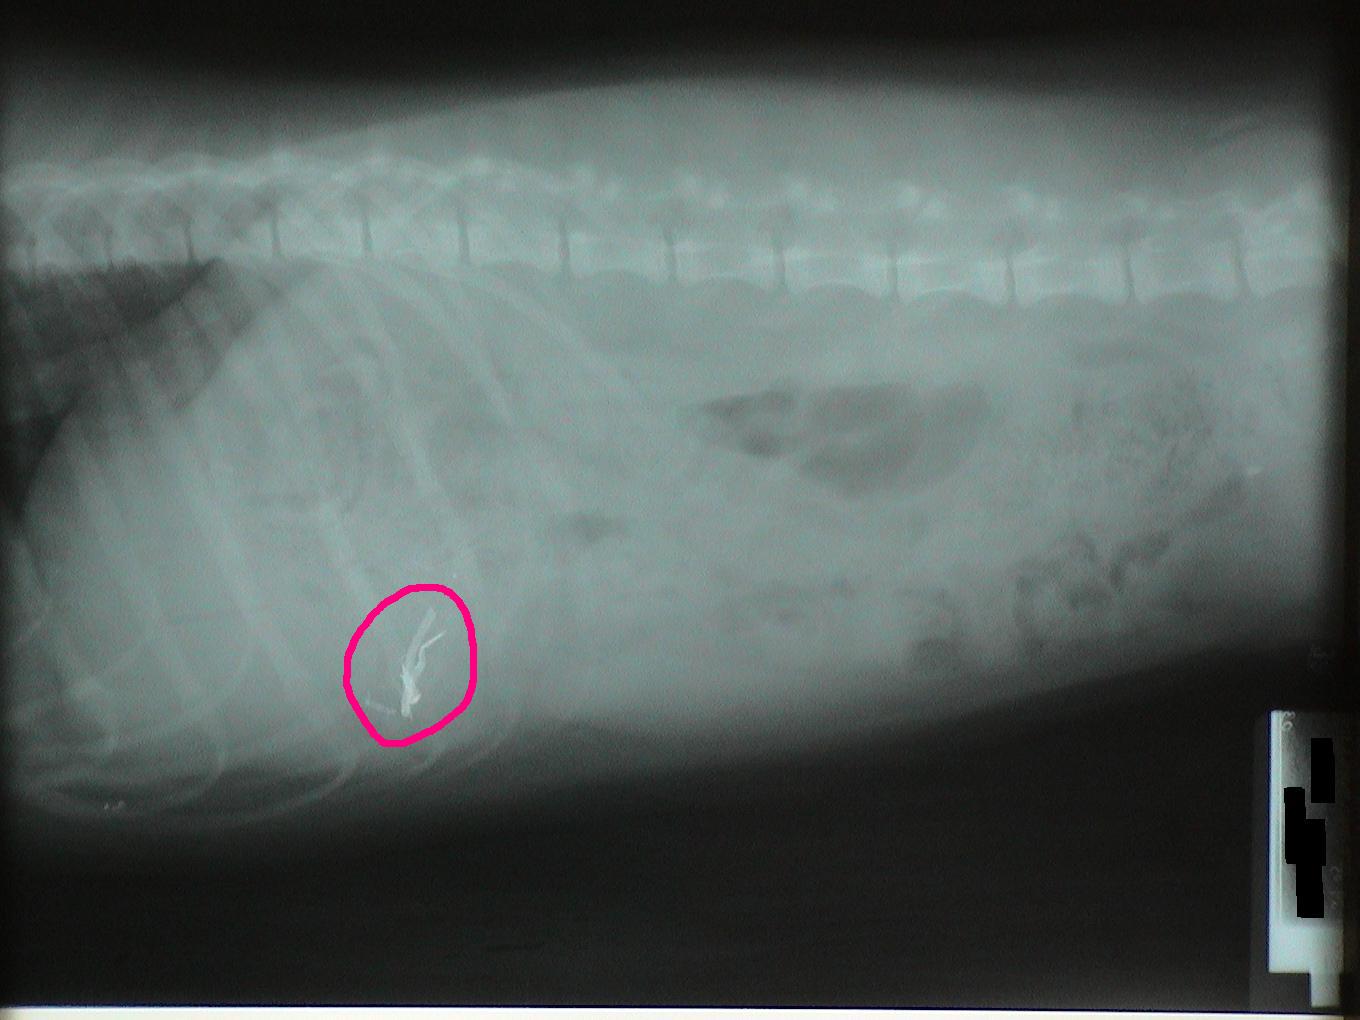

Let's identify the foreign bodies in each of these x-rays.